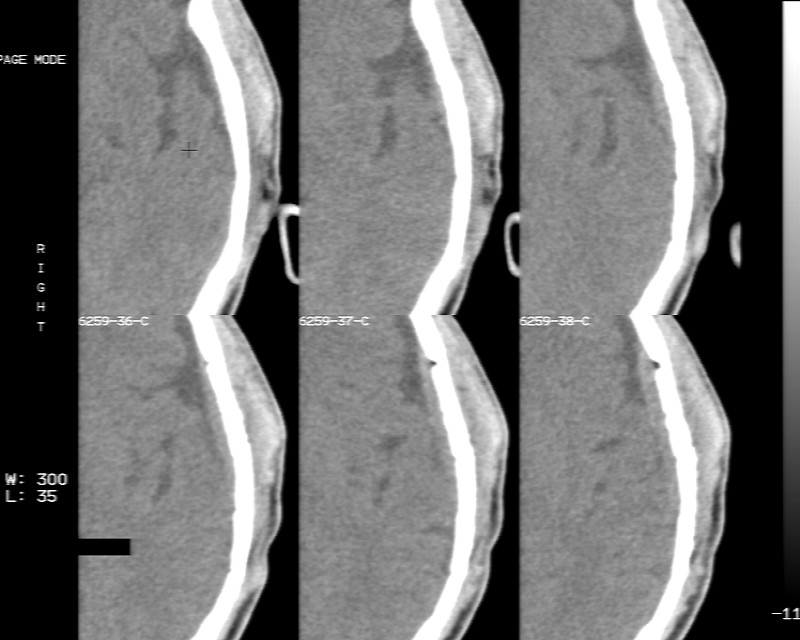

m70y, 2个月前发现左颞部有'包'隆起,近来自觉增大,无外伤无任何不适症状而就医,触诊包块质地较硬无移动无波动无皮温升高,胸片示右上肺陈旧结核....,ct扫描见左颞骨翼板局部内外骨板骨质破坏,似筛孔状,外板侧有骨膜线状增生,伴局部软组织丘状肿块,内板下梭形肿胀硬膜增厚翘起......颅内脑无异常.考虑骨良性病变 1.低度骨感染.   2.嗜酸性肉芽肿. 3.不排外骨结核...建议其穿刺活检,但患者失踪,追踪到结果定将公告.请大家分析.

左颞骨内板不光滑,密度减低,内板下可见新月形的软织密度影。脑实质轻度受压,外板外见膨胀形稍高密度影。考虑嗜酸性肉芽肿。建议增强扫描

骨质密度不均,骨质两旁均有软组织影,考虑嗜酸性肉芽肿可能性大,同时也不能除外转移瘤。